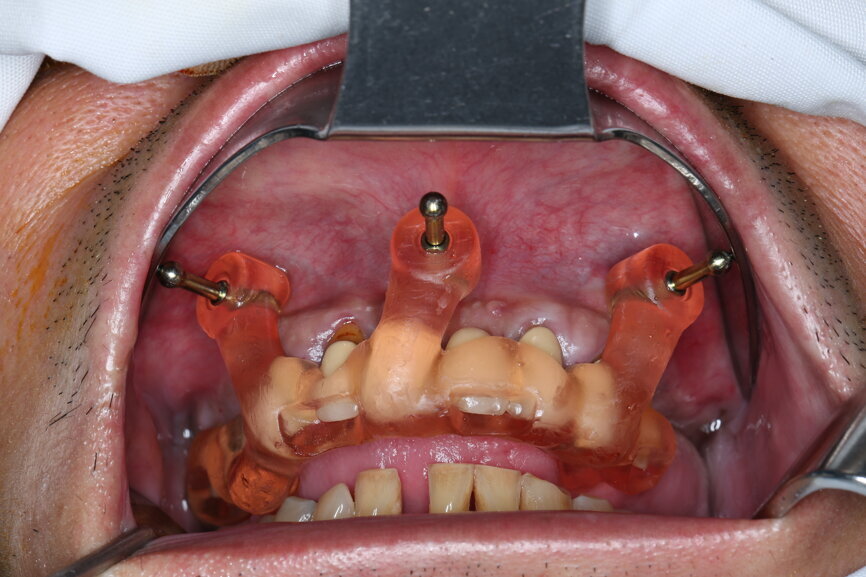

On the day of surgery, we prepared for the surgical protocol provided by the implant planning software, which guided us on the drilling sequence and the use of the appropriate instruments for the implant bed preparation (Figs. 30a & b). After the fixation pins had been allocated, teeth #17, 16, 15, 13, 12, 22, 23 and 24 were atraumatically extracted and alveolectomy was performed using a bone reduction guide (Figs. 31–36). Four implants (Straumann BLX; regular base; diameter: 4.5 mm; length: 12.0 mm) were placed, two straight implants in the anterior and two titled implants in the posterior. All the implants were stabilised to a torque of 50 Ncm (Figs. 37–43), and the SRAs were placed on top. The SRAs on the posterior implants had an angulation of 30° (diameter: 4.6 mm; gingival height: 3.5 mm) and on the anterior implants an angulation of 17° (diameter: 4.6 mm; gingival height: 3.5 mm; Figs. 44 & 45).